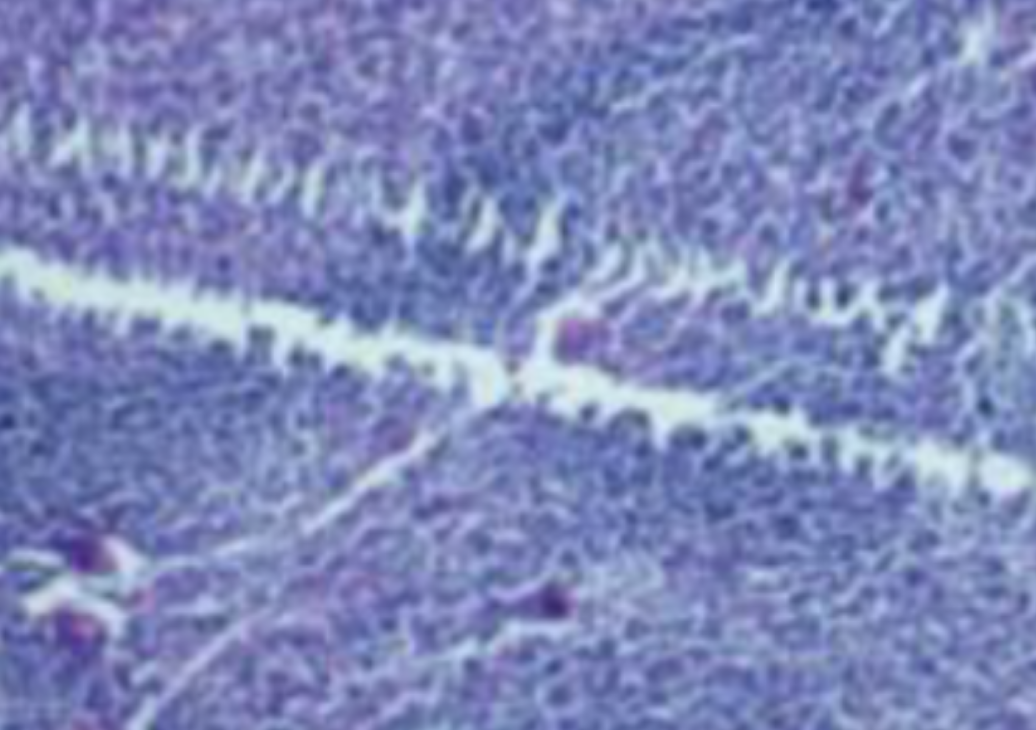

HE染色,全称苏木精-伊红染色法(Hematoxylin and Eosin staining),是最常见的组织切片染色技术之一,用于在显微镜下观察和分析组织或细胞的结构和形态。

虽然HE染色是最常见且最基础的染色技术之一,😭但在实验过程中,很容易出现各种情况导致染色切片质量参差不齐。所以,小编根据以往实验经验,给大家整理归纳出了15个HE染色中的常见问题,还包含问题原因分析以及解决方法哦~

形成原因:切片经梯度乙醇处理后没有完全脱水,导致二甲苯透明、中性树胶封固后残留大量水分。 解决方法:首先移去盖玻片,用二甲苯溶解封固剂如中性树胶,再将切片置入无水乙醇内,待切片重新脱水完全后,用二甲苯透明处理,中性树胶封固。要注意所有用于脱水和透明的液体,在使用一定时间后,应及时更换。 二、细胞核呈红、棕色 形成原因:苏木精染色液过度氧化,切片在苏木精染液染色后返蓝不足。 解决方法:每次染色之前检查苏木精染色液的染色能力,发现苏木精染色液氧化过度应及时更换。此外,切片经苏木精染色后,要给切片以足够的蓝化时间,蓝化过程可用流水、温水、弱碱性溶液(如稀氨水或0.2%碳酸氢钠)等处理。 三、切片在脱蜡后出现大片白色斑点 形成原因:由于烤(烘)片温度太低,切片上的组织蜡膜在脱蜡前没有充分烤(烘)融化。或是因为切片在二甲苯液中停留时间不足,或二甲苯使用过久,造成的脱蜡不彻底。 解决方法:若是由于切片烤(烘)温度低所致,可以先用二甲苯去除切片上的封固胶,然后重新用二甲苯脱去切片上的石蜡,再进行后续染色。若是由于切片在脱蜡的二甲苯中停留时间不足或脱蜡二甲苯使用过久浓度不足所致,则需将切片退回到二甲苯中,停留较长时间,或更换二甲苯液体重新脱蜡,再入乙醇重新脱二甲苯,入0.5%盐酸水溶液褪色后,重新HE染色。 四、细胞核苍白暗淡,即苏木精染色太淡 形成原因:切片在苏木精染色液停留时间太短;苏木精染色液过度氧化,失去染色能力,不能再继续使用;分化步骤处理时间过长;固定不及时。此外值得注意的是,若骨组织细胞核暗淡,大多是脱钙过度造成的。 解决方法:切片重新染色。如果组织在酸性固定液(如Zenker、Bouin)或非中性缓冲甲醛液固定时间过长,细胞核染色能力将减弱,需增加其在苏木精染色液的时间,或用一些方法增加组织的嗜碱性,以改善细胞核的着色。例如,上述组织玻片可以使用Weigert铁苏木精染色液。如果组织是用Zenker液固定的,可将切片脱蜡后放在5%碳酸氢钠溶液3~4h,流水冲洗5min后染色。如果组织是用Bouin液固定的,可将切片脱蜡后放在5%碳酸锂1h,流水冲洗10min后染色。 五、细胞核过染,苏木精染液占据了细胞质 形成原因:玻片在苏木精染色液停留时间过长,或是切片太厚、分化步骤时间太短。 解决方法:如果不是因为切片太厚(用显微镜仔细上下微调,只有一二层细胞核层次),就需将切片进行脱色、漂白、重新染色,适当调整染色和分化时间。但如果确定是由于切片太厚导致的细胞核过染,则需要重新切片。 六、伊红着色淡 形成原因:可能是伊红染液pH值大于5,也可能是蓝化液残留过多,切片太薄,或是切片经伊红染色后在乙醇脱水时间过长。 解决方法:检查伊红染液pH值,必要的话,用乙酸将其调节在4.6~5.0之间,从而使伊红染色色彩艳丽。此外,确保每次蓝化步骤完成后,使用的弱碱性溶液被充分洗去,玻片上没有残留的弱碱性溶液。最后,检查切片的厚度,且脱水时不要让切片在低浓度乙醇中停留时间过长,因为含水多的低浓度乙醇会将切片伊红的颜色分化掉。 七、细胞质过染、分色不足 形成原因:伊红染色液浓度太高,特别是存在焰红燃料、四溴四氯荧光素钠。切片在伊红染色时间过长,或是切片在伊红染色后经乙醇脱水步骤时时间太短,而使乙醇分化伊红的作用不能产生,都能够使细胞质过染。 解决方法:适当稀释伊红染色液,减少伊红染色时间,或使切片在乙醇脱水等步骤时,停留时间相对均匀。同样,也要检查切片的厚度是否合适。 八、切片中出现蓝黑色沉淀物 形成原因:苏木精染色液中的金属膜黏附在玻片上。 解决方法:染色前仔细过滤苏木精染色液,建议使用半氧化苏木精染色液,如Gill苏木精染色液,可以避免过多的金属膜产生。 九、光镜下切片某些区域难以聚焦 形成原因:盖玻片上可能有封固切片的封固剂。 解决方法:移去盖玻片,重新用干净的盖玻片封片。检查切片封片方法,是人工手工封法,还是机器自动封法,如有问题及时调整。 十、封固剂从盖玻片与载玻片之间的缝隙回缩 形成原因:盖玻片弯曲或不平整,或是封固剂含二甲苯过多,稀释过度。 解决方法:移去盖玻片,重新找一张盖玻片,用干净的封固剂封片。如用手工封片法,保证在封固结束时,封固剂容器盖子为紧闭状态。且尽量使用小的容器盛装封固剂,一旦封固剂太黏稠,就可以选择废弃。 十一、细胞核呈灰蓝状态 形成原因:可能由于组织处理温度过高、过热,在液体石蜡中停留的时间过长。或是固定时间太短后,直接在高浓度的乙醇中进行了脱水处理。 解决方法:理论上来说,仅在组织浸蜡步骤才进行加热,组织不能在热蜡液中停留太久。如果由于某些原因不能进行下一步包埋处理,可将组织连同塑料包埋盒一并放置在室温空气中,冷却凝固,以备包埋。待需要包埋时再重新加温直至石蜡融化即可。组织在处理前必须确保固定良好,脱水最好能从低浓度的乙醇开始。 十二、类色素的点状结晶和黑色光滑细胞核 形成原因:这种裸核改变是因为切片封片前放置在空气中的时间太长,以至于二甲苯挥发,切片干燥。 解决方法:移去组织切片上的盖玻片和封固剂,重新处理。将切片水洗数分钟,然后重新脱水、透明、封固。封片过程中要保持组织切片的轻度湿润,尽量不要让其干燥。 十三、染色过淡或过浓 解决方法:如果染色过淡,可以增加染色剂的浓度、延长染色时间或更换新鲜的染色剂;如果染色过浓,则应减少染色剂的浓度或缩短染色时间。 十四、切片出现叠加褶皱 形成原因:新购买的玻片洁净度不够、用镊子撑开切片时操作不够熟练未能平整伸展,或玻片表面有油脂,切片粘贴不牢。另外,烤片时间不足、烤片温度过低或切片过厚造成切片脱落,都会造成重叠或有皱褶的情况。 解决方法:新购买的玻片最好能用硫酸清洁液浸泡一晚,然后流水冲洗干净。在适宜的温度下烤片时间宁长勿短,保证有充足的烤片时间和温度。另外,切片刀要锋利,才能切出厚薄适宜的切片,保证切片不会因为过厚而脱落。 十五、组织残缺不全或有刮划痕迹 形成原因:组织残缺不全是由于切片时修整蜡块时深度不够、组织没有全部暴露于切面。切片的刮划痕迹是由于切片刀的刀锋有缺口、包埋的组织有异物,或是钙化组织、骨组织及包埋石蜡有沙粒造成的。 解决方法:修整蜡块时保证组织块全部暴露于切面,切片时保证切片刀的锋利没刀口。同时在组织取材时去除手术异物和钙化组织。最后,骨组织要完全脱钙,这样可以保证切片的完整和平整美观。 *注:由于实验中导致结果出现误差的原因多种多样,以上内容仅供参考,具体根据实际情况进行判断。